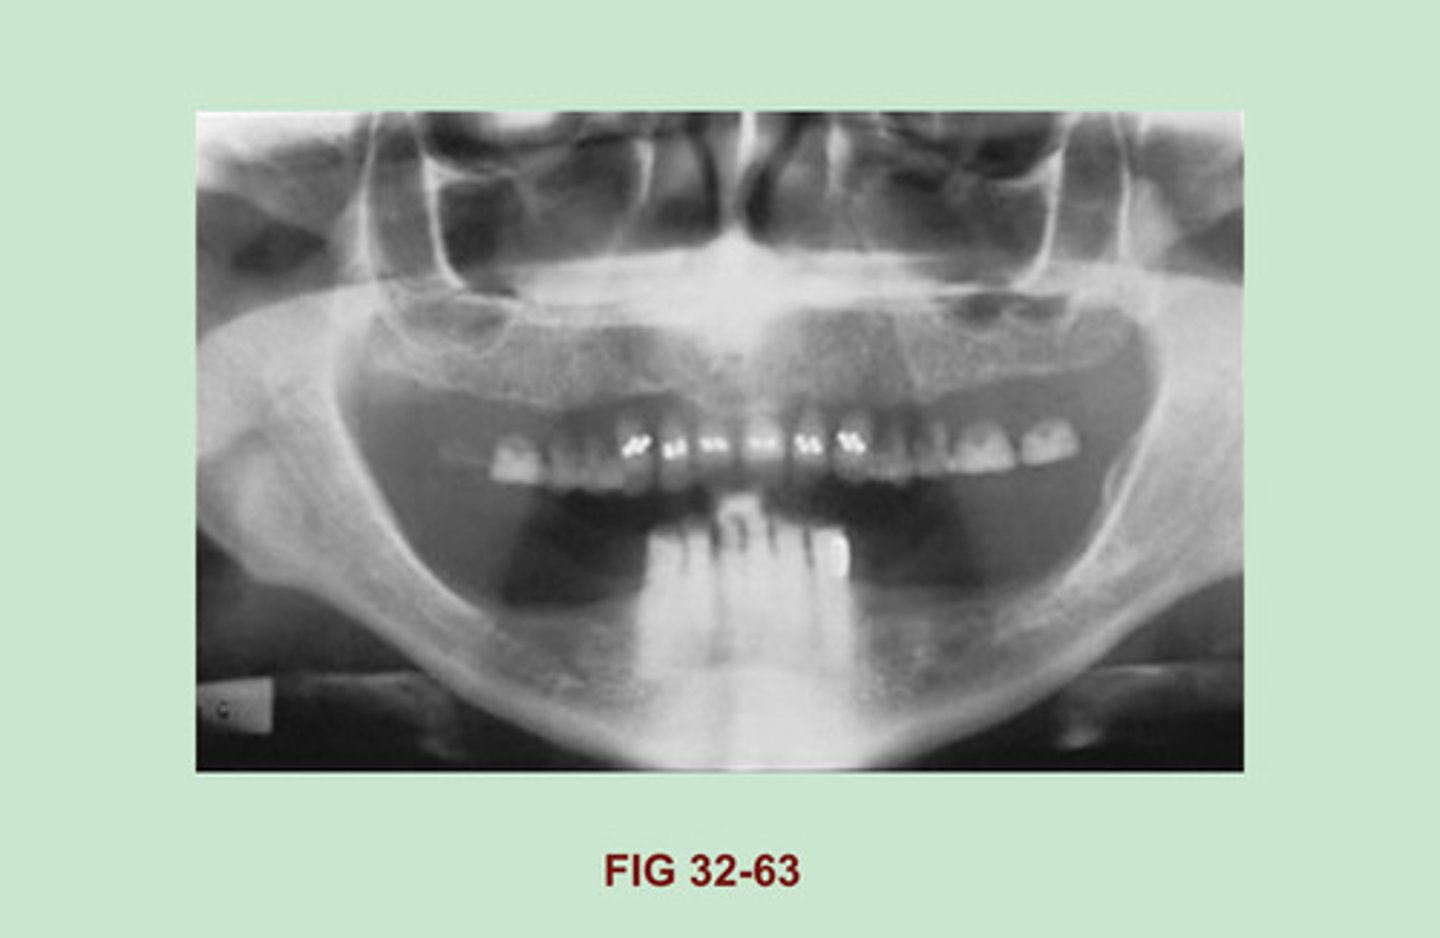

EXPLAIN why the MAXILLARY TEETH in this dental image appear to be "FLOATING". (Figure 32-63).

Dentures were not removed prior to exposure.